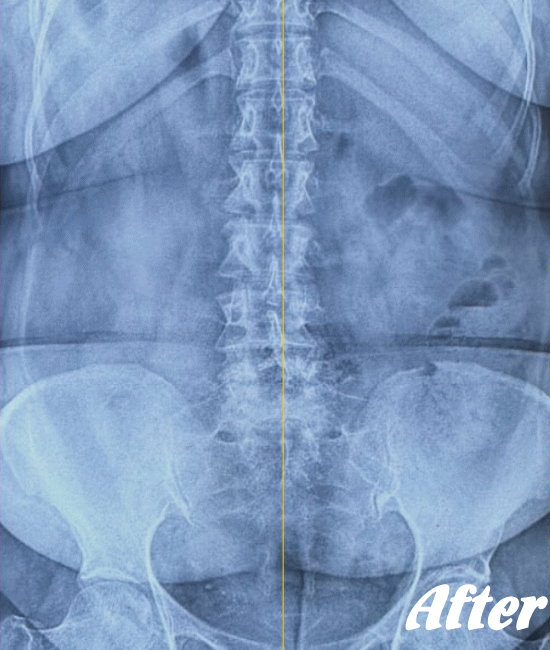

レントゲン、CT、MRIといった画像診断などで坐骨神経痛の原因となる病気(例えば、ヘルニアや脊柱管狭窄症など)が見つかれば、その治療を行います。原因となる病気が見つからない場合は、第一選択肢として、保存療法が適応されます。

HALOカイロプラクティック☆平和島整体院では、仙腸関節や腰、股関節などの部位を解剖学的に正しい状態へ戻すことで、筋肉をゆるめ、関節の詰まりを広げ、圧迫されてしまった神経を解放し、痛みや痺れのない状態へと回復させます。

また、首(頚椎)の歪みにより腰に負担がかかることで坐骨神経痛を発症することもあるため、首も調整します。

ただし、歩行に支障をきたすような激しい痛みの場合は、「股関節のズレが酷い」「腰椎の椎間が詰まっている」「ヘルニアが突出している」「仙腸関節が炎症を起こしている」…等々、通常よりも症状が悪化しているため施術回数が長引くことをご理解いただいたうえで、当院へお越し下さい。